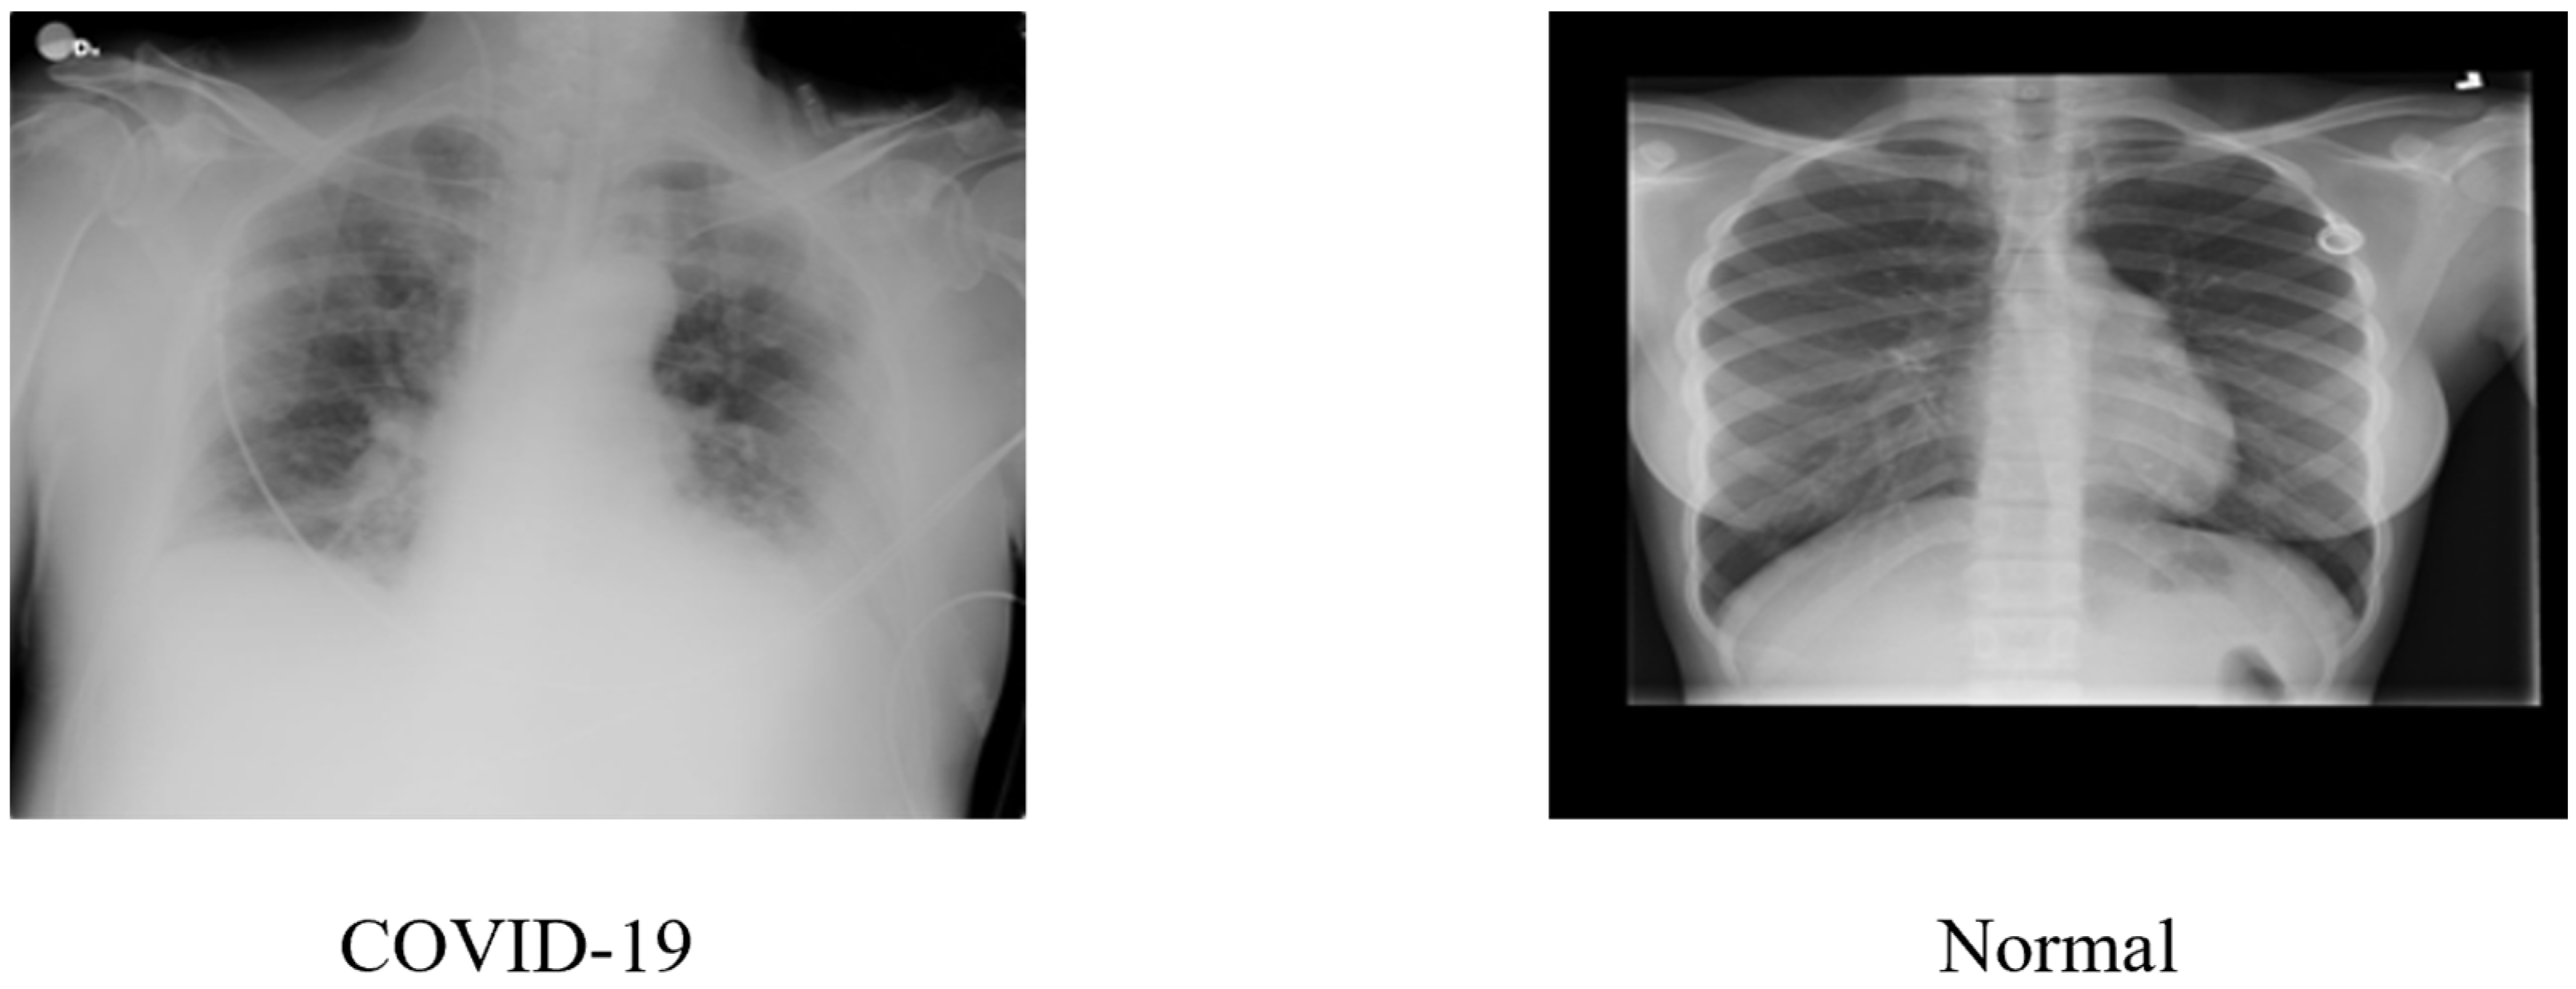

3.1. Dataset Description